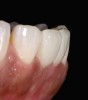

Fig. 2  Preparations for laminate veneers.

Figure 2

The clinical application of this protocol is illustrated in a patient situation where laminate veneers were placed on four maxillary incisors to replace lost tooth structure and restore function and esthetics. The failing restorations were removed, followed by a conservative veneer preparation (Figure 1 and Figure 2). The bonding surfaces of the feldspathic porcelain veneers were acid-etched with hydrofluoric acid for 2 minutes (Figure 3) and thoroughly rinsed. Then a silane coupling agent was applied (Figure 4). Figure 5 demonstrates the situation after bonding the veneers to the teeth with a composite resin luting agent.